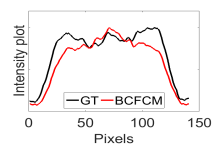

The calculated correlation coefficient (), SNR, as well as CNR values for all tested methods in the synthetic phantom experiment are shown in Table II. As seen in Table II, the proposed NCBC method achieved the highest , CNR as well as SNR values when compared to that of other tested methods. Visual results from the bias-corrected DW-MR synthetic phantom data produced using different tested methods is shown in Fig. 2(c-i). It can be observed that the MCBC, LEMS, and proposed NCBC method were able to achieve the best level of bias correction when compared to the other tested methods. This is particularly apparent in the peripheral zone (PZ) of the prostate gland as highlighted using red ROIs in Fig. 2(a-i), where intensity inhomogeneities are still present to a significant degree in the bias-corrected phantom data produced using the LS, SCIC, SGD and BCFCM methods, while strong inhomogeneity correction performance is achieved using MCBC, LEMS, and the proposed NCBC method. Furthermore, it can be observed that NCBC exhibited minimal intensity inhomogeneities when compared with MCBC and LEMS, particularly in the area that is highlighted using Red ROIs. To better represent the outperforming of proposed NCBC method in terms of bias correction using synthetic phantom, the data intensity profiles corresponding to the drawn blue line in Fig. 3(a) are shown in Fig. 3(b) for uncorrected data (red color plot) versus ground truth data (black color plot) and in Fig. 3(c-i) for corrected data using different tested methods (red color plots) versus ground truth data (black color plots). As the intensity profiles of Fig. 3(b-i) show, NCBC method was resulted in an intensity profile with the most flatness and less amount of variation compared to the intensity profiles of uncorrected image as well as reconstructed images using other tested methods as such confirms the better performance of proposed NCBC method in terms of bias field correction.